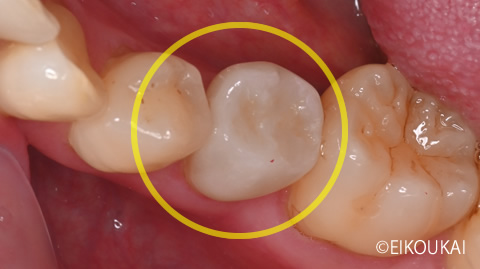

治療内容 左下5番に虫歯があり、虫歯除去から根の治療、被せ物をつけるところまで治療をしました。

被せ物は見た目が綺麗で今後虫歯になりにくいセラミッククラウンで行いました。金額 左下5 セラミッククラウン 118,800円 治療期間 1ヶ月 通院回数 6回 リスク/副作用 強い噛み合わせ、強い噛み締め食いしばりで欠けるリスクあり。